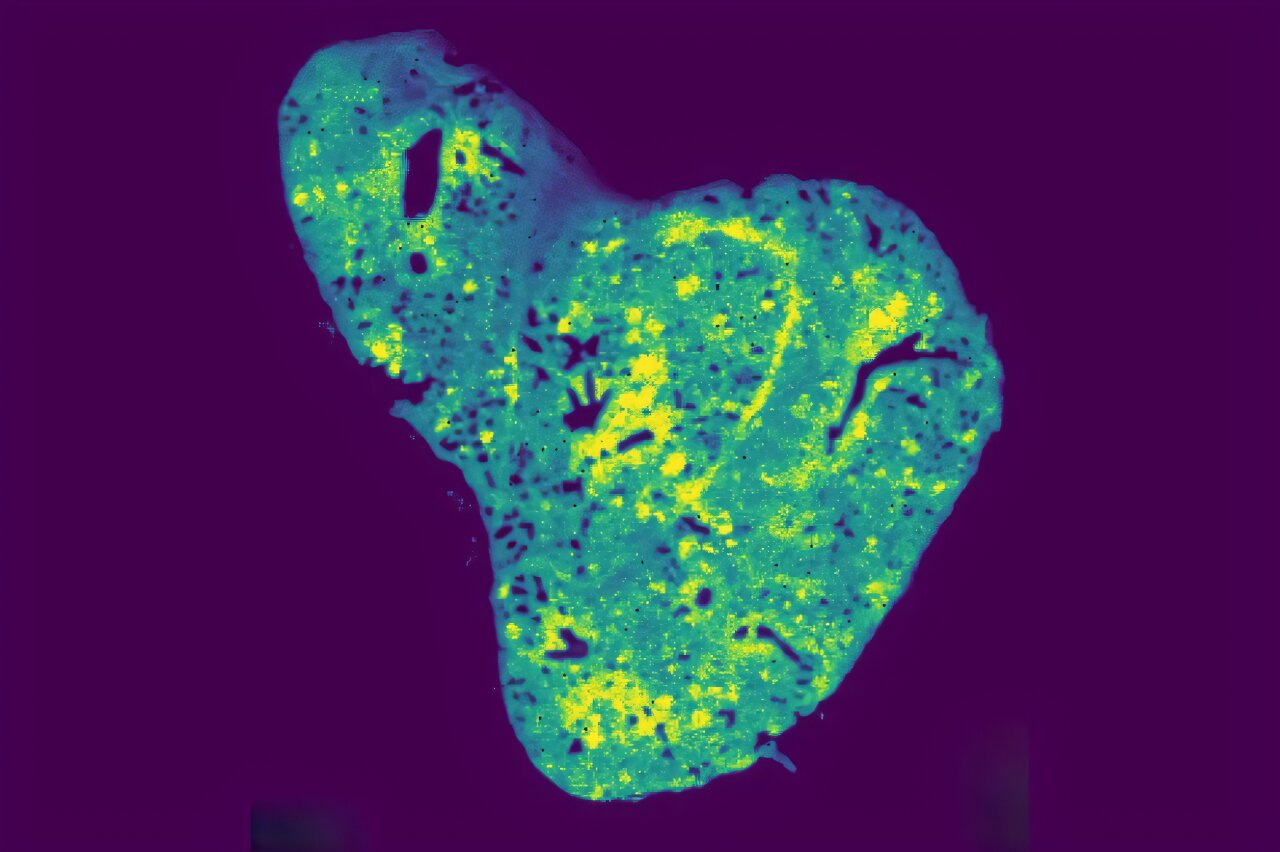

Researchers are investigating how cancer uses extracellular vesicles to colonize new organs and are creating artificial liposomes that mimic these vesicles to observe uptake by cancer cells in real time, with the goal of delivering targeted therapies and ultimately blocking metastasis while improving drug delivery.